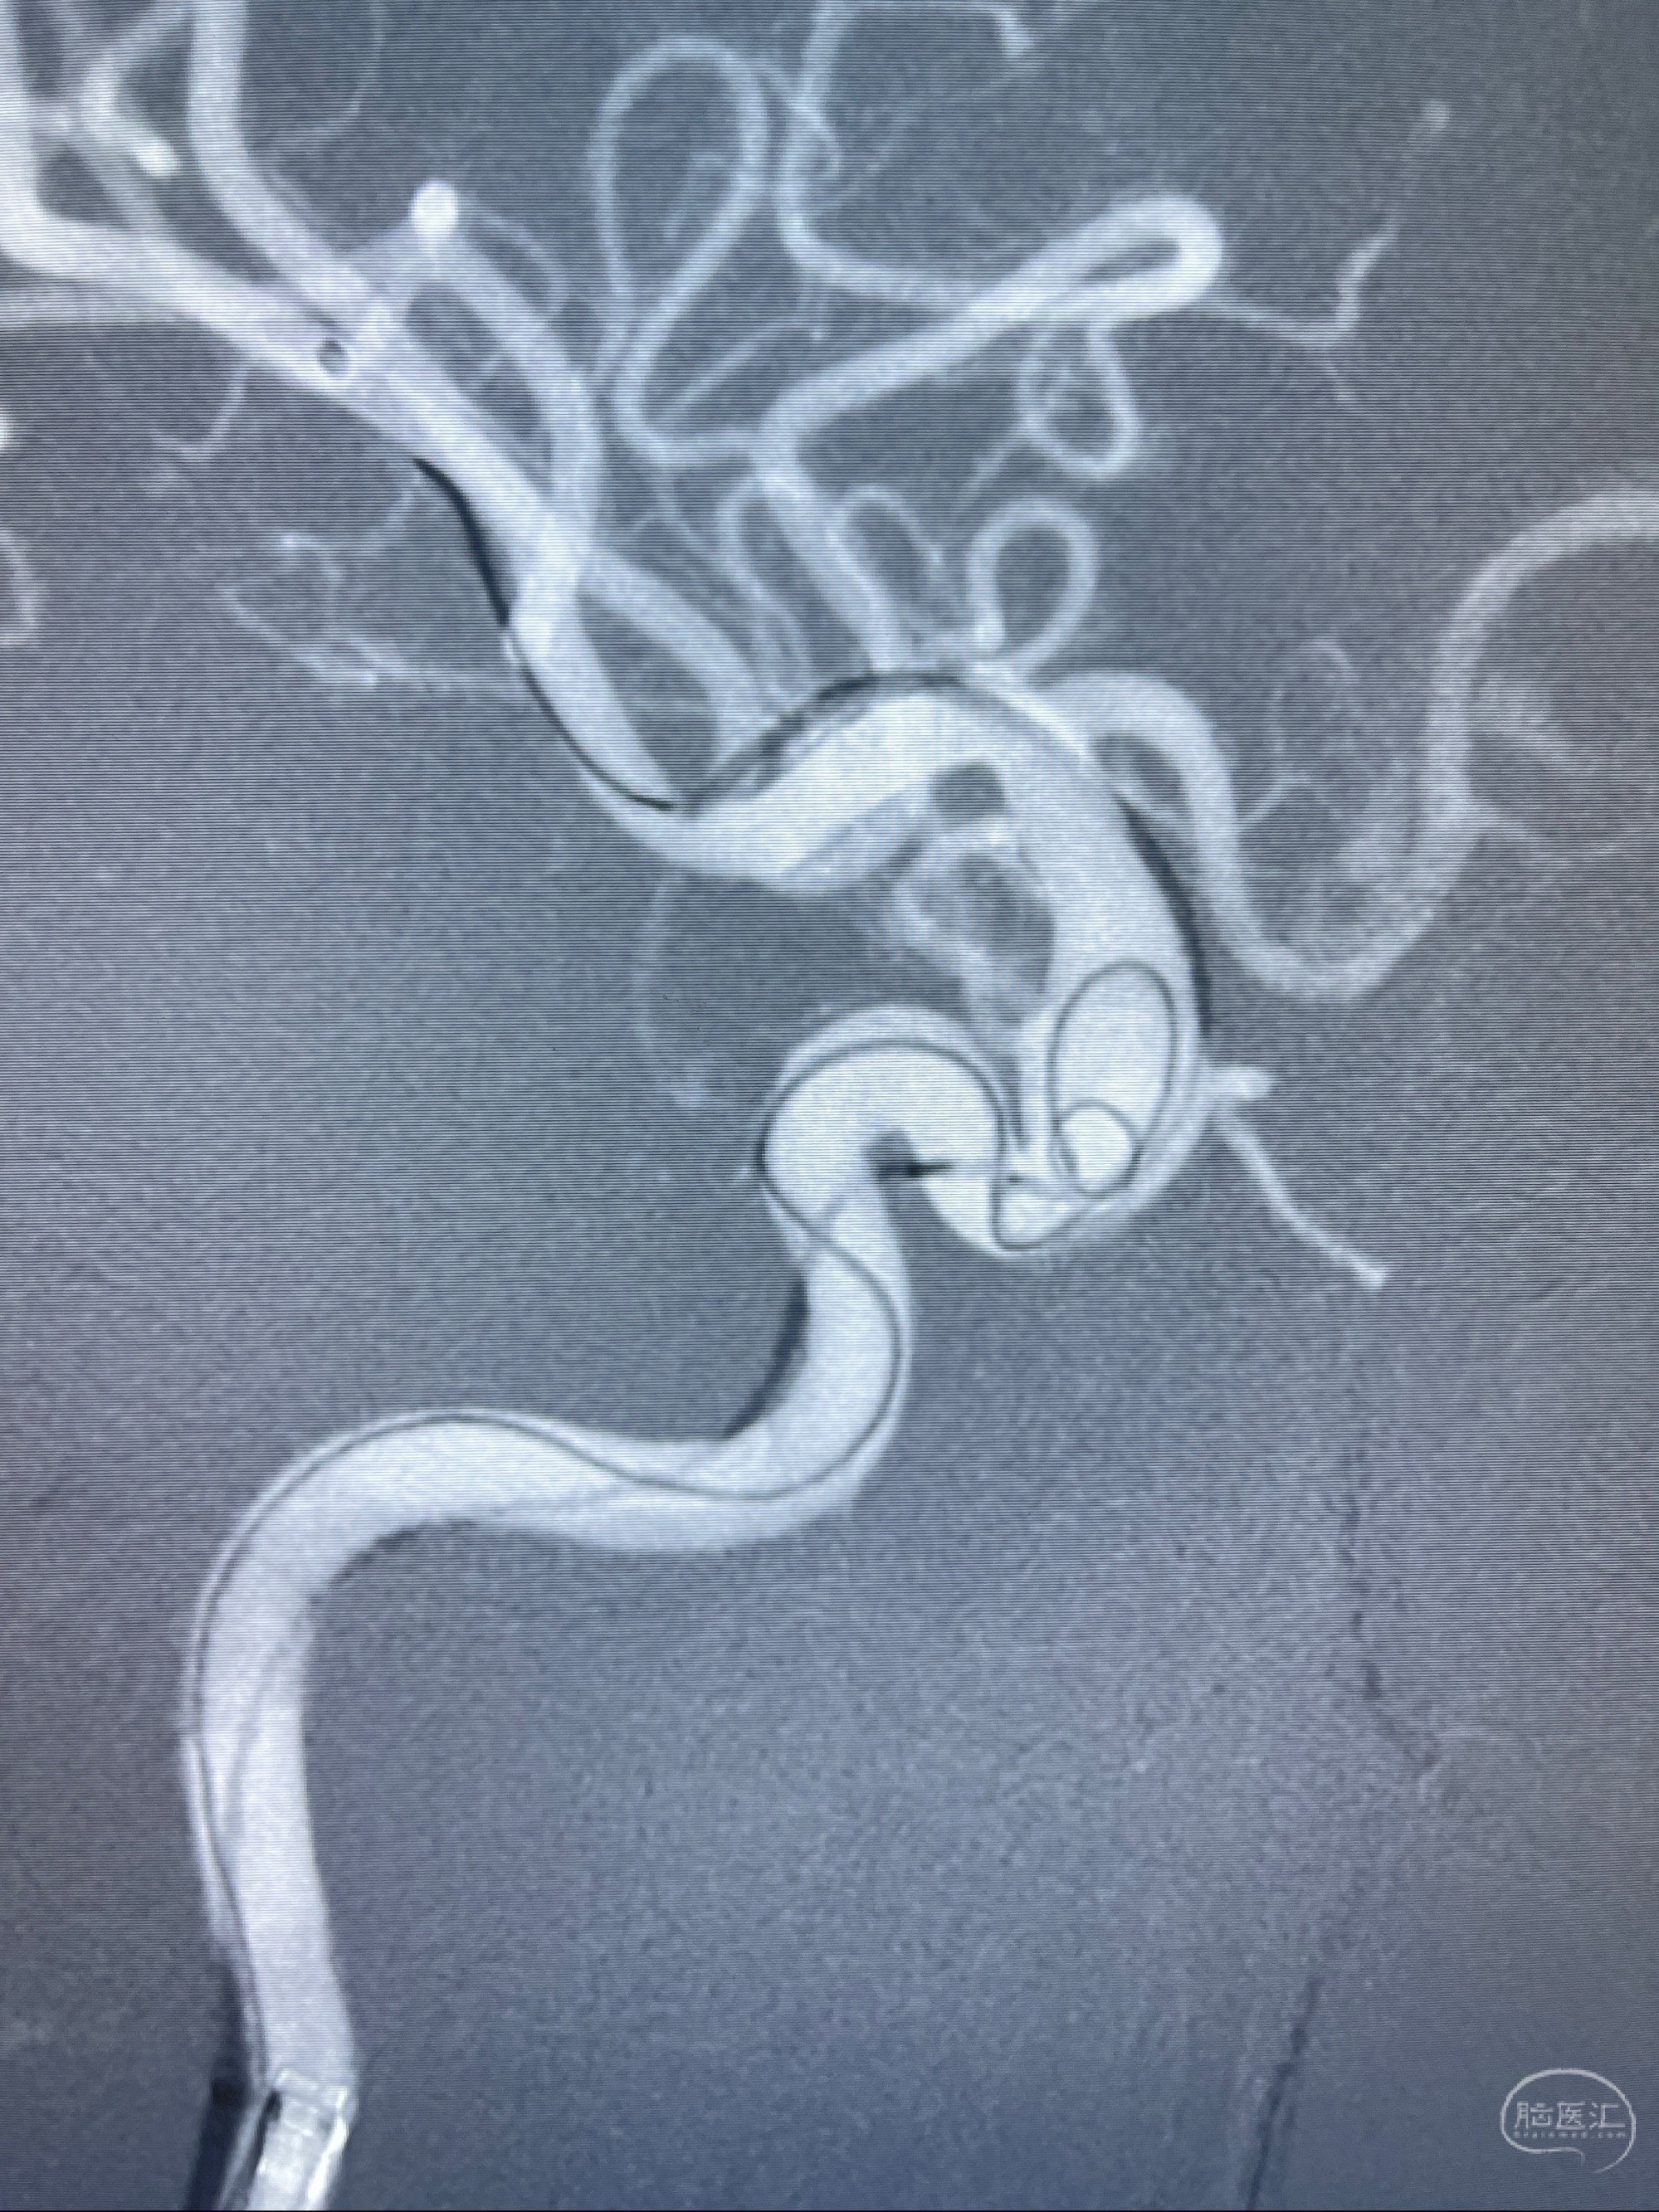

2023-08-01全麻下行双侧颈眼动脉瘤支架辅助栓塞

- pipeling4.5-20mm

- pipeline 4.0-20mm

手术顺利,麻醉苏醒佳,遵嘱动作

术后即刻CT